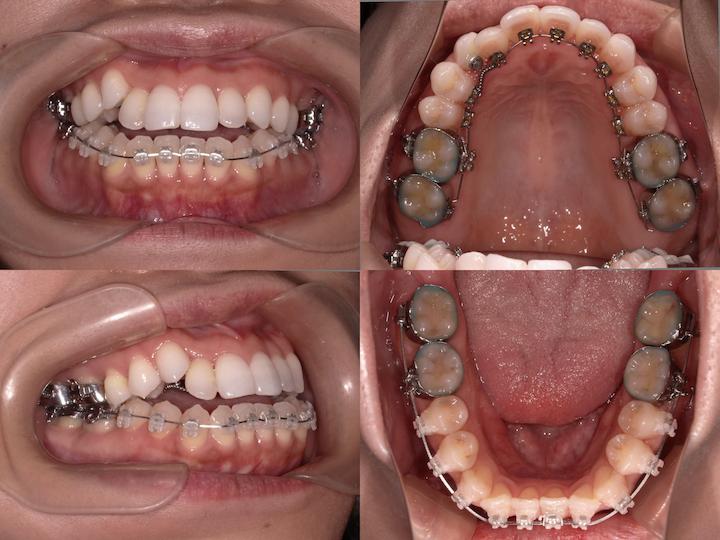

治療結果

上下顎前歯部の叢生は完全に改善され、犬歯も適切な位置に配列されました。また、AngleⅡ級臼歯関係も改善し、機能的かつ審美的に良好な咬合状態を獲得することができました。

口元の形態も治療前の良好な状態を維持しており、患者様からも高い満足度をいただいております。